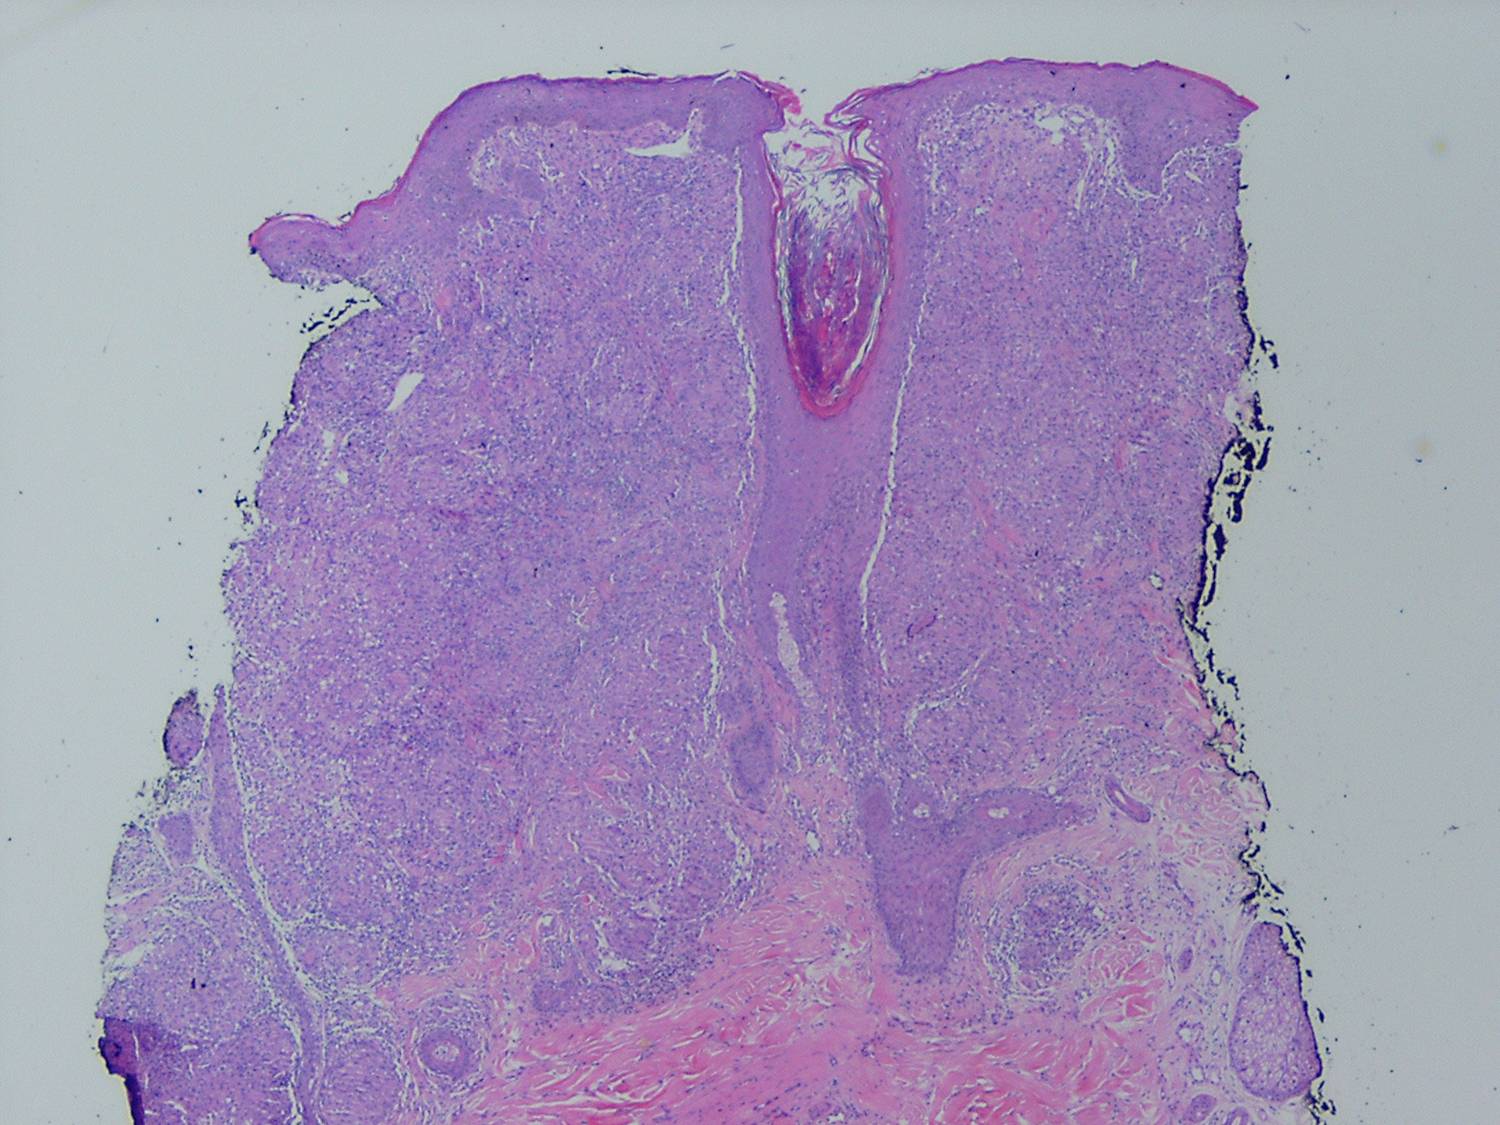

Like lesions in other organs, the cutaneous lesions of chronic, persistent sarcoidosis are characterized by the presence of circumscribed collections of epithelioid histiocytes-so-called epithelioid cell tubercles-which show little or no necrosis .

The papules, plaques, and lupus pernio-type lesions show variously sized aggregates of epithelioid cells scattered irregularly through the dermis with occasional extension into the subcutis (. In the erythrodermic form, the infiltrate shows small granulomas in the upper dermis intermingled with numerous lymphocytes

and, rarely, also giant cells . Typical sarcoidal granulomas are found in the ichthyosiform lesions , in ulcerated areas , and in atrophic lesions . Verrucous sarcoid exhibits prominent associated acanthosis and hyperkeratosis . Biopsies of

hypopigmented sarcoid may reveal granulomas, which may have a perineural component or fail to reveal granulomas . In subcutaneous nodules, larger epithelioid cell tubercles lie in the subcutaneous fat .

In typical cutaneous lesions of sarcoidosis, the well-demarcated islands of epithelioid cells contain few, if any, giant cells. Those that are present are usually of the Langhans type. A moderate number of giant cells can be found in old lesions. These giant cells may be large and irregular in shape. In a minority of cases, giant cells contain asteroid bodies or Schaumann bodies . Asteroid bodies , which are more common, are star-shaped eosinophilic structures that, when stained with phosphotungstic acid-hematoxylin, produce a center that is brown-red with radiating blue spikes . Schaumann bodies are round or oval, laminated, and calcified, especially at their periphery. They stain dark blue because of the presence of calcium. Neither of these two bodies is specific for sarcoidosis: They have been observed in a variety of other granulomas, including those of leprosy, tuberculosis, foreign-body reactions, and necrobiotic xanthogranuloma .

Classically, sarcoid has been associated with only a sparse lymphocytic infiltrate, particularly at the margins of the epithelioid cell granulomas . Because of the scarcity of lymphocytes, the granulomas have been referred to as "naked" tubercles. However, lymphocytic infiltrates in sarcoid may occasionally be dense, as in tuberculosis . Occasionally, small foci of fibrin or necrosis showing

eosinophilic staining is found in the center of some of the granulomas . A reticulum stain of sarcoid reveals a network of reticulum fibers surrounding and permeating the epithelioid cell granulomas. If the granulomas of sarcoidosis involute, fibrosis extends from the periphery toward the center, with gradual disappearance of the epithelioid cells . Fibrosis, however, is minimal to absent in most examples of sarcoidosis, with the exception of the morpheaform variant, where it is prominent {191}. Other features that may sometimes be seen include elastophagocytosis, increased dermal mucin, and lichenoid inflammation .